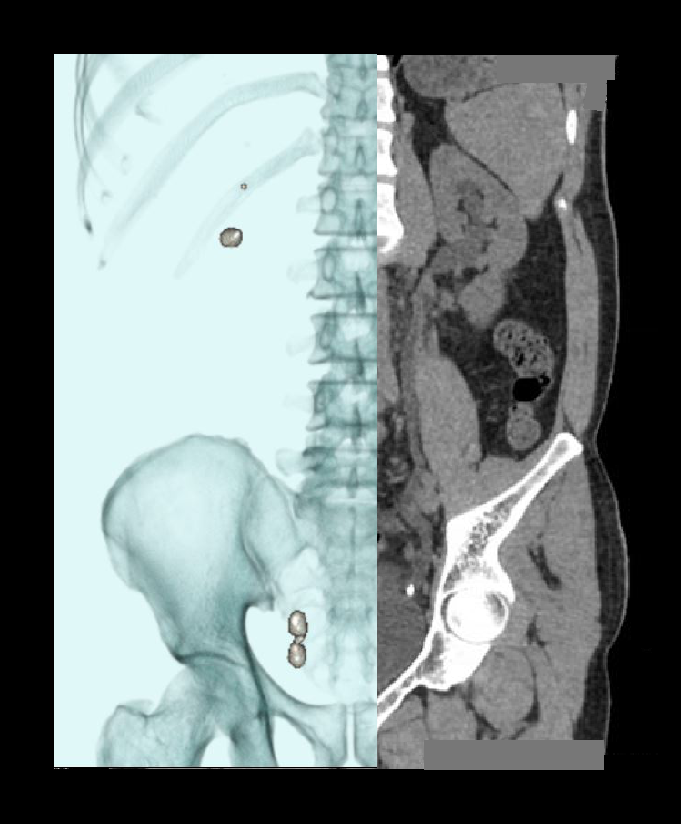

- Layered 3D images to show stones with respect to the lumbar spine.

- Curved MPR images to show both ureters.

- Measurements in length and width of each calculus.

- Measurement in Hounsfield unit (HU) of each calculus.